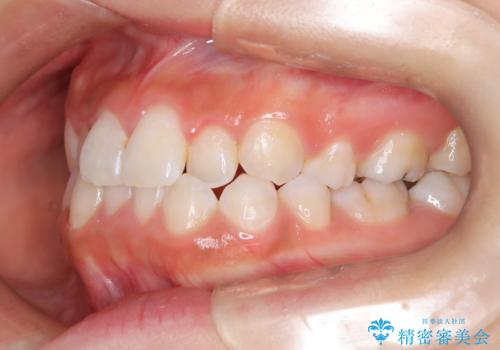

- 子供のころに矯正治療をされていたが、後戻りをしてしまったという20代女性の患者様です。上顎左右の2番が、咬合時に下顎の歯よりも内側に入っているクロスバイトという状態でした。奥歯の咬合関係は変えずに、マウスピース矯正にて前歯の並びを綺麗なアーチに仕上げました。再度後戻りしてしまうリスクを軽減させるために、リテーナー(保定装置)をお渡ししています。